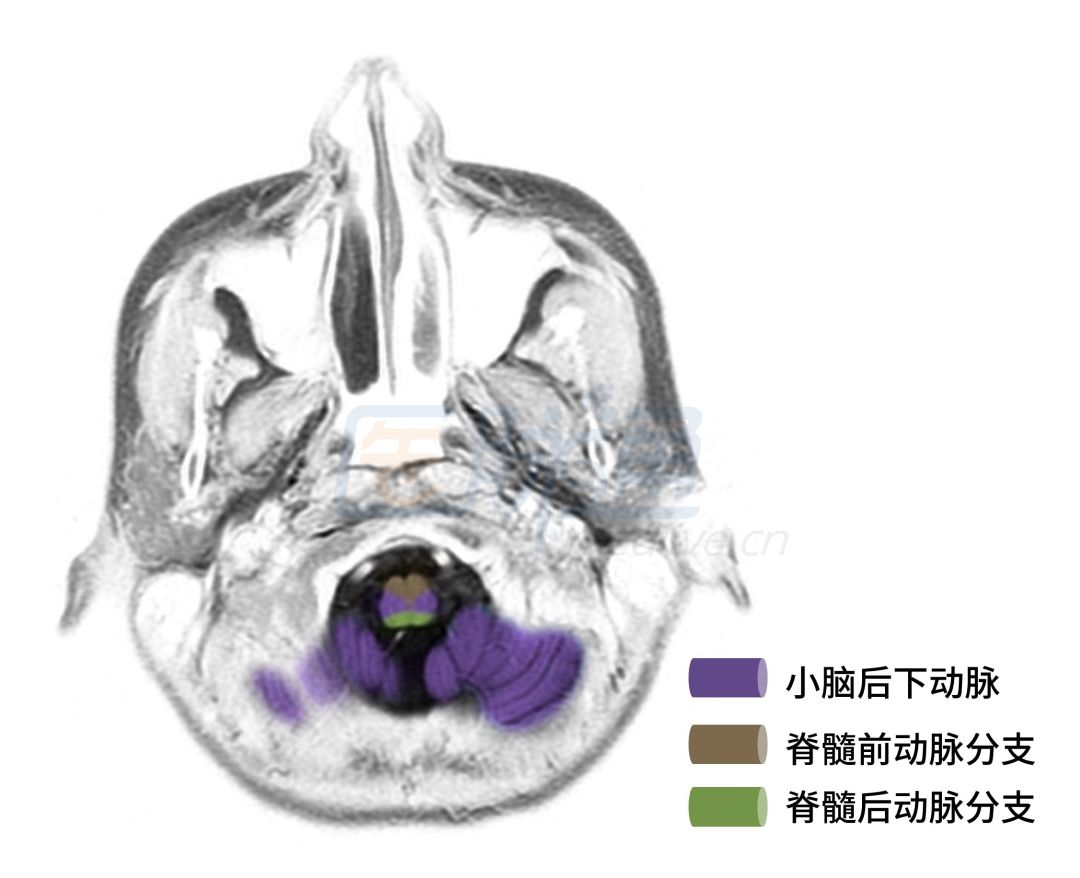

图3 延髓下部层面

图3、4显示的层面主要是延髓和小脑血管供应区域。

❖ 脊髓前动脉:供应脊髓前2/3,闭塞可引起病灶水平以下上运动神经元瘫痪、分离性感觉障碍和膀胱直肠功能障碍。

❖ 脊髓后动脉:供应脊髓后1/3,闭塞可引起病灶水平以下深感觉障碍。

❖ 基底动脉:后部分支供应延髓内侧,闭塞可引起同侧舌肌麻痹和萎缩,对侧上下肢中枢性瘫痪以及触觉、位置觉、振动觉减退或丧失,即Dejerine综合征。

❖ 小脑后下动脉:供应延髓,闭塞可引起延髓背外侧综合症;供应小脑半球的下面以及扁桃体,闭塞可引起同侧肢体共济失调。